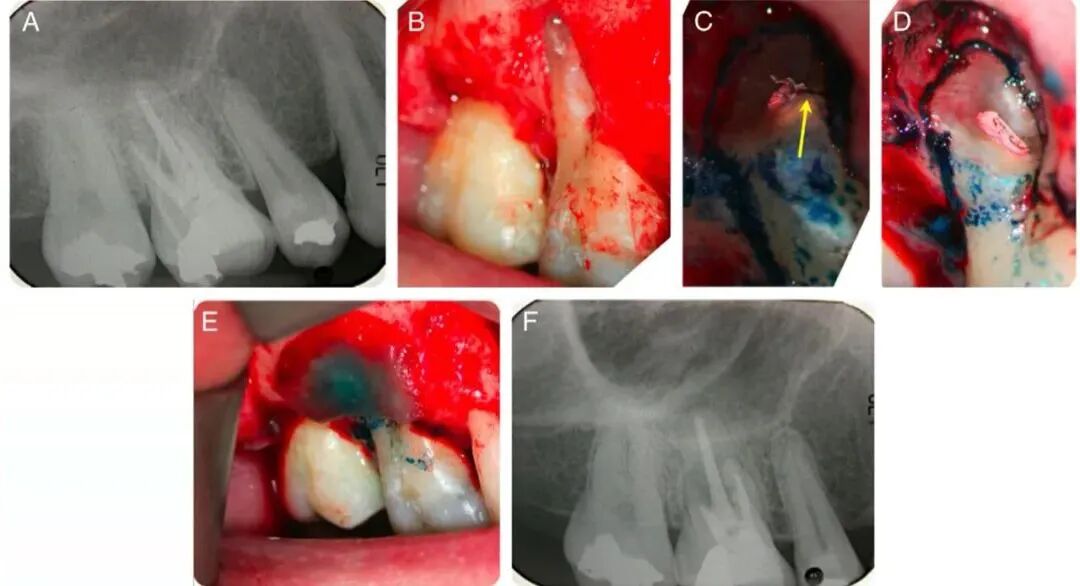

此外,在制作假壁时,除了复合树脂外,特殊情况下亦可选用蓝玻。下图为根管治疗期间蓝玻暂封及制作假壁图:

在显微根管外科手术过程中,通过亚甲蓝染色后在高倍镜下检查,可以观察到根充物与根管壁之间是否存在间隙或渗漏,是否存在根管遗漏、根尖牙本质微裂、管间峡区等复杂的解剖结构以及是否存在牙根纵裂,切除后的牙根断面是否平整等。

下图为根尖手术亚甲蓝染色后发现远颊根上有牙根纵裂和磨除裂隙后的情况。